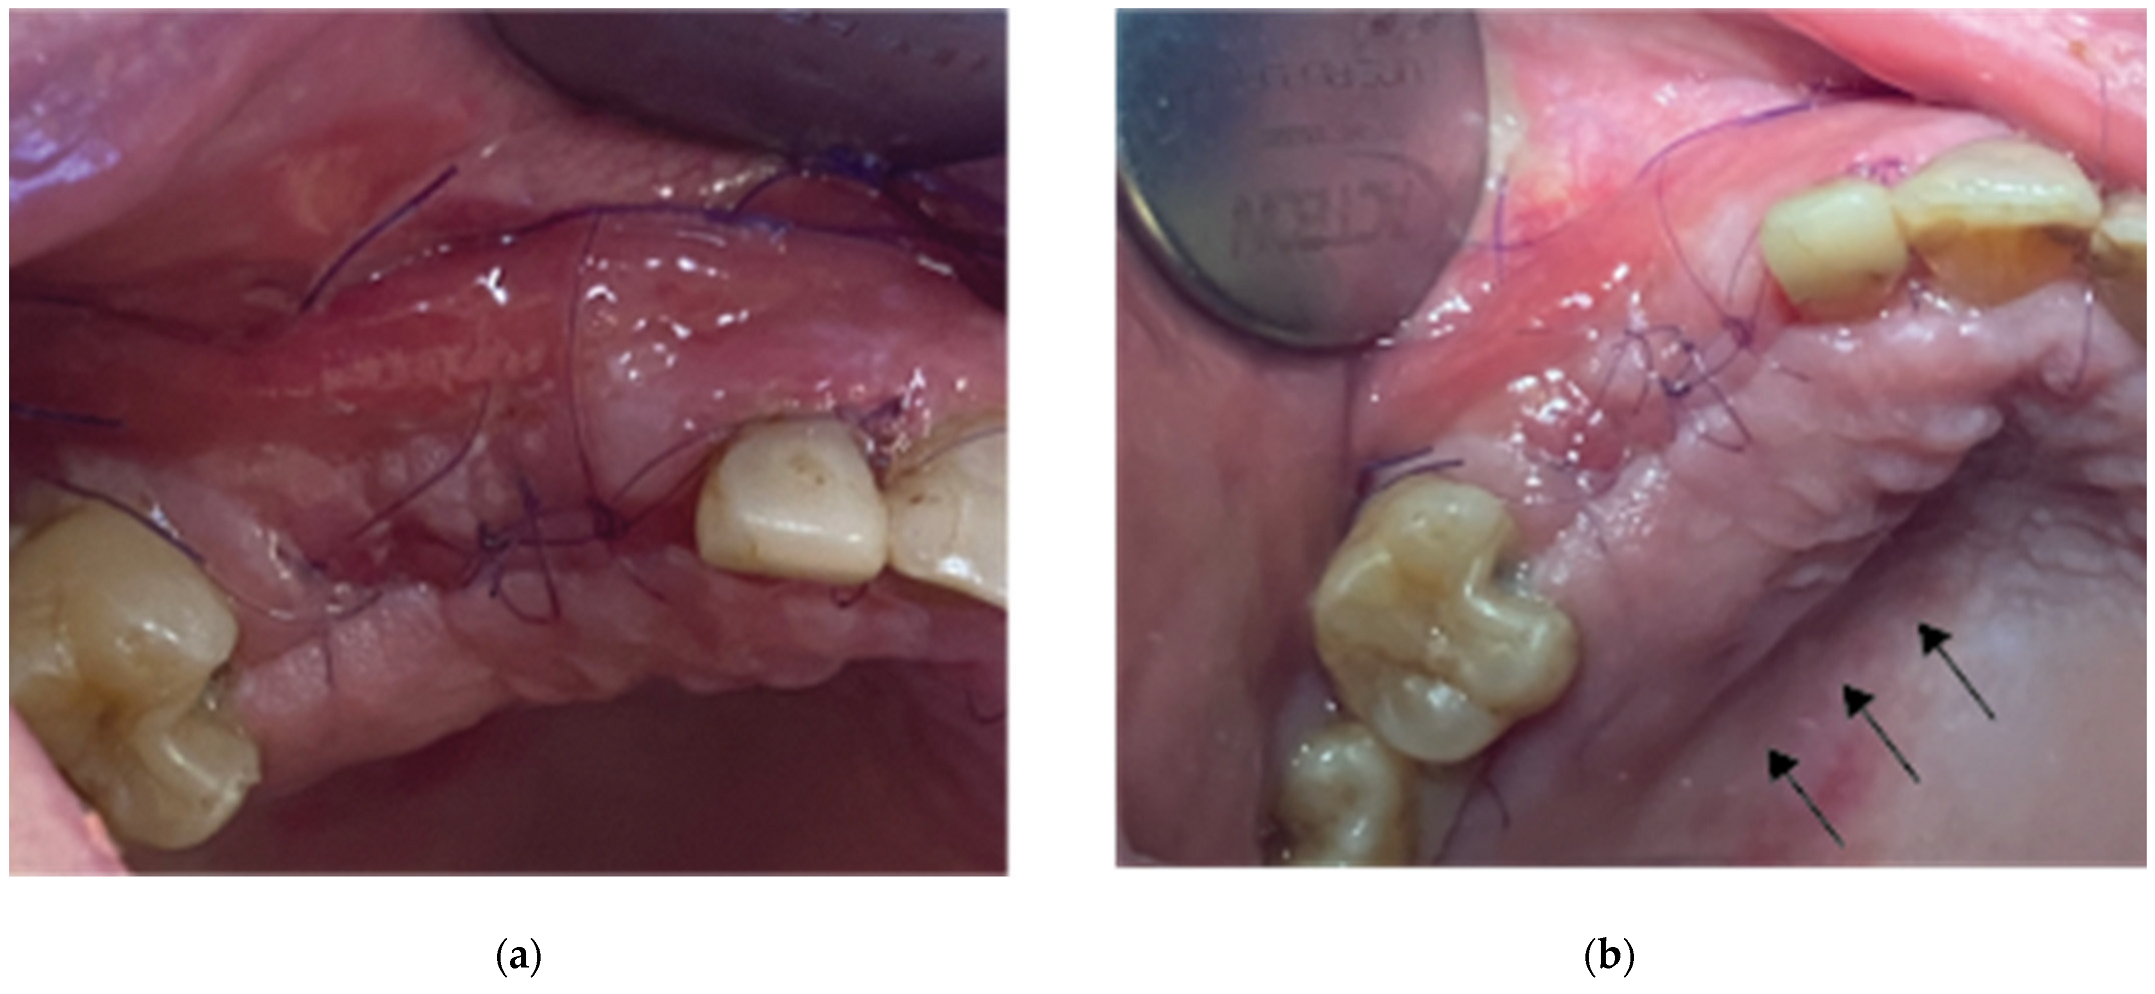

Figure 10. Clinical Situation 2 Weeks Post op: (a) Lateral view with primary closure with the 2 layers of sutures, (b) Occlusal view with arrows revealing the palatal incision location.

Flap closure over the barrier and the abutments was performed with a palatal release incision and 2 layers of sutures as follows (Figure 10):

• A palatal incision parallel to the alveolar ridge and located apically nearly 15mm from the marginal palatal soft tissue, leaving the periosteum intact, was performed prior to the placement of sutures. Then a split thickness preparation below the palatal flap was performed till the dissected area reached the incision limits. After confirmation of the communication between both entries the palatal flap coronal advancement was possible ensuring a primary closure.

• An intermediate layer of horizontal mattress monofilament absorbable Glycolon 4.0 adaptation sutures (Resorba, Nuremberg, Germany) were placed below the muco-gingival line to secure an additional stabilization of the cortical barrier on both buccal and palatal sides and coronal advancement of both flaps.

• A superficial layer of Vertical mattress (placed at the papillary areas between the adjacent, to the augmentation site, teeth) along with simple interrupted Glycolon 5.0 (Resorba, Nuremberg, Germany) closure sutures (placed at the inter proximal abutment areas) provided primary flap closure and papilla stabilization on their initial preoperative position.

• A superficial incision performed with a 15 blade deep in the vestibule was finally used to reduce the muscle pull during the healing postoperative period.